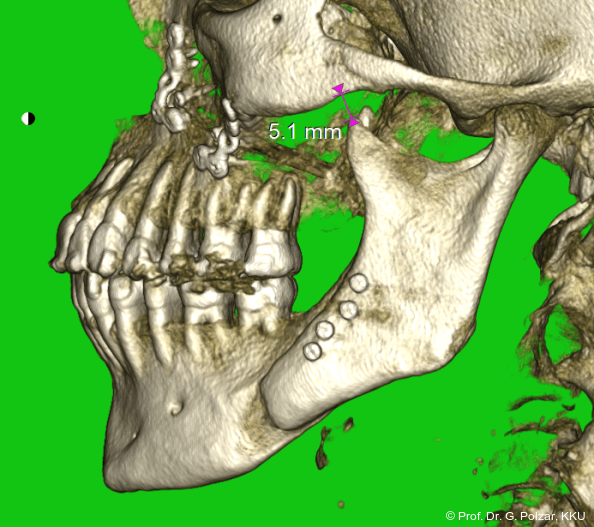

Im Sagittalschnitt zeigen beide Kiefergelenke eine deutlich anteriore Position. Der dorsokraniale Abstand betrug rechts 7,0 mm und links 5,8 mm. In der PEP waren sie im lateralen Bereich ca. 1 mm kleiner als in der Mitte der Sagittalprojektion (Abb. 6a–d).

Trotz destruktiver KG-Anatomie mit Peeking, das meint vereinfacht, dass der Kondylus exponiert unter dem Gelenkhöcker liegt, was ein Zeichen für eine ungünstige Gelenkstellung sowie starke Belastung des vorderen Bereichs ist, und verschobener Gelenkscheibe (craniale Kompression) hat sich die Okklusionssituation nach der Behandlung so verbessert, dass die Patientin subjektiv deutlich we­niger Beschwerden hat und sich insgesamt wesentlich wohler fühlt. Der Luftweg hat sich an der engsten Stelle (Isthmus faucium im Bereich der Tonsillen) von 122 qmm auf 202 qmm erweitert (Abb. 15a–d).

Nach der Umstellungsosteotomie mit der UK-­Vorverlagerung kann die Patientin besser zubeißen. Bei maximaler Interkuspidation in neutraler Okklusion befinden sich nun beide Kiefergelenke in zentraler Po­sition zur Gelenkpfanne. Der geringe Abstand des Caput mandibulae zur Schädelgrube lässt auf eine Diskusverlagerung schließen (Abb. 20a+b).